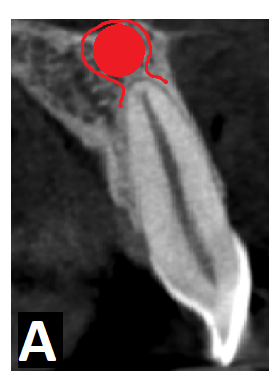

Obecnie wyróżnia się torbiele okołowierzchołkowe prawdziwe (true cysts) (ryc. 1a) oraz torbiele okołowierzchołkowe kieszonkowe (pocket cysts) (ryc. 1b). Torbiele prawdziwe nie mają połączenia z kanałem korzeniowym i mimo prawidłowo przeprowadzonego leczenia endodontycznego nie ulegają najczęściej wygojeniu i w związku z tym wymagają chirurgicznego usunięcia. Torbiele kieszonkowe mają z kolei połączenie w kanałem korzeniowym i dlatego w większości przypadków po prawidłowo przeprowadzonym niechirurgicznym leczeniu endodontycznym ulegają wygojeniu (2, 3). Badania histologiczne Naira i wsp. (4) oraz Ricucciego i wsp. (5, 6) wykazały, że oba rodzaje torbieli występują z podobną częstotliwością (tab. I). To oznacza, iż połowa torbieli korzeniowych może ulec wygojeniu po konwencjonalnym leczeniu kanałowym (7).

Ryc. 1 a. Schemat obrazujący torbiel prawdziwą (światło torbieli wyścielone całkowicie nabłonkiem nie ma połączenia z kanałem korzeniowym); b. schemat obrazujący torbiel kieszonkową (światło torbieli wyścielone nabłonkiem ma połączenie z kanałem korzeniowym).